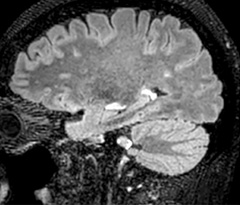

A two year follow-up scan of a CPA meningioma using both Ingenia 3.0T without CS and Ingenia Elition 3.0T with Compressed SENSE allows for a nice comparison to demonstrate the protocol improvements achieved on the Elition: 3D FLAIR has a shortened scan time, improved SNR and still the same spatial resolution. BrainView (3D T1 TSE) has improved spatial resolution and SNR with shortened scan time. For 3D T2 Drive the spatial resolution has been improved. 3D THRIVE used to have an interpolated 0.8 mm slice thickness, but true thickness at 1.6 mm, so that axial slices displayed a decent quality, but reformats were suboptimal.

Compressed SENSE is used on Elition to improve spatial resolution and reduce the non-interpolated slice thickness to allow smoothly reformatted images. Total scan time (adding SmartBrain and an additional b2000 diffusion) was 13:19 on Ingenia, and is now reduced to 10:42 on Ingenia Elition.

Ingenia Elition 3.0T with Compressed SENSE

3D FLAIR (with Compressed SENSE)

3D FLAIR

1.0 x 1.0 x 1.0 mm*

2:50 min.

3D TSE T1w (with Compressed SENSE)

3D TSE T1w

2:10 min.

3D T2w Drive (with Compressed SENSE)

3D T2w Drive

0.7 x 0.7 x 0.7 mm*

2:52 min.

3D T1w THRIVE (with Compressed SENSE)

3D T1w THRIVE

0.7 x 0.7 x 0.8 mm*

1:30 min.

*true voxel size, without interpolation